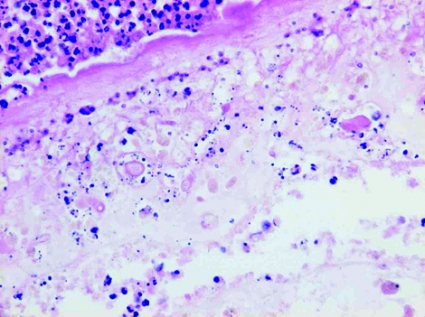

Beslut fattades om neurokirurgisk exstirpation av lesionen. Operatören beskrev en spelkulestor, hård och välavgränsad förändring samt en påtaglig reaktion i hinnorna. Histopatologisk undersökning av förändringen visade en solitär, välavgränsad process (8 6 mm i snittytan) med en bred, fibrös kapsel och runt den en uttalad infiltration av inflammatoriska celler, främst plasmaceller och eosinofila leukocyter. I det nekrotiska cystinnehållet urskildes cystvägg och en central skolex (huvud) stadd i nedbrytning (Figur 3 och Figur 4), således ett för neurocysticerkos diagnostiskt fynd.

Tyvärr undersöktes likvor inte avseende eosinofili. Intestinal taeniasis påvisades inte. Som differentialdiagnos diskuterades bakteriell hjärnabscess och neoplastisk förändring. Exstirpation av cystan gav diagnostisk klarhet och samtidigt terapi; detta dock på bekostnad av en hjärnlesion, som antas vara större än vid naturlig degeneration av parasiten eller vid antiparasitär behandling.